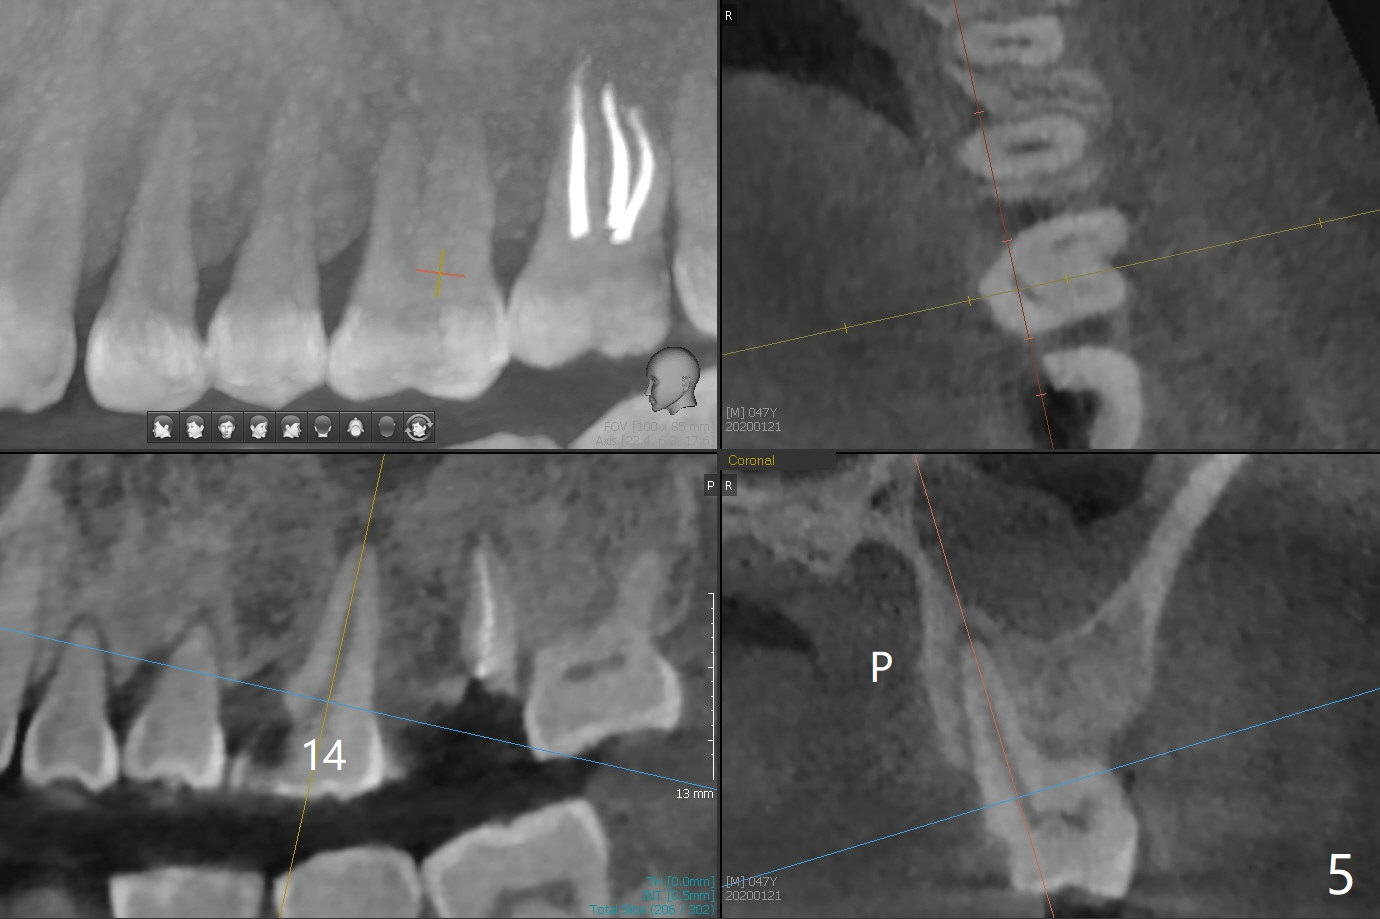

A 47-year-old man has pain at #2 and 15, while #14 has mesiolingual subgingival fracture (Fig.1). #2 is deemed non-salvageable by an endodontist, whereas RCT is finished at #15. When the patient returns for restoration, he reports that the filling is out at #15. In fact it has subcrestal fracture (Fig.2), while #14 equicrestal and difficult to restore (Fig.3). Although the patient agrees to have implants at #2 and 15, DB bone loss at #2 makes it difficult for implant (Fig.4). Use FC implant for primary stability. Insert a small piece of cotton pellet or healing screw and pack sticky bone around the implant before placing a temporary abutment. The latter will form a large gingival cuff, which makes it easy to place pair abutment without interference from the crestal bone. Screw loosening will be reduced. In fact there is PARL of the palatal root of #14 (Fig.5). A FC implant will be also placed at #15 for the same reason (Fig.6).